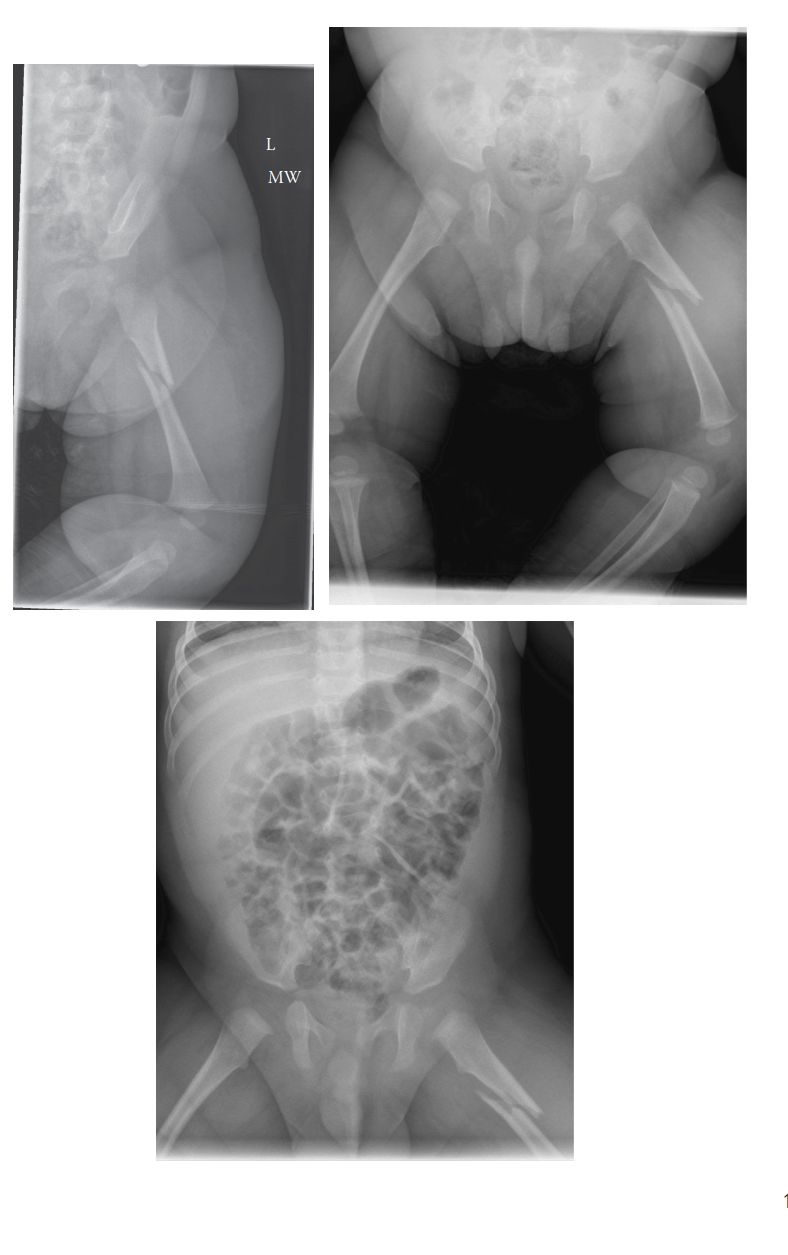

Characteristic Fracture Patterns Indicative of NAI

- Metaphyseal Corner Fractures (MCFs) / Bucket-Handle Fractures: These are considered pathognomonic for NAI, particularly in infants and young children. They result from shear and torsional forces applied to the physis, often from violent shaking or pulling of an extremity. The injury involves the primary spongiosa, leading to a small fragment avulsed from the metaphysis. Radiographically, they appear as a crescent-shaped or bucket-handle lucency parallel to the physis. Common locations include the distal femur, proximal tibia, and proximal/distal humerus. The biomechanical mechanism requires forces that exceed the strength of the developing physeal-metaphyseal junction, which is cartilaginous and relatively weak compared to ligaments in young children.

- Rib Fractures: Especially posterior and posterolateral rib fractures, multiple rib fractures, or fractures at different stages of healing. These are highly specific for NAI, resulting from anterior-posterior compression of the chest (squeezing) or direct impact. Due to the pliability of pediatric ribs and the protection offered by surrounding musculature, significant force is required to fracture them. Posterior rib fractures are particularly suspicious as they are difficult to sustain accidentally.

- Multiple Fractures in Various Stages of Healing: This is a cardinal sign of ongoing abuse. Radiographs may reveal both acute and healing fractures, indicating repeated traumatic events over time. This finding necessitates a full skeletal survey.

- Skeletal Survey: This is mandatory for any child under the age of two with suspicious fractures, and often recommended for children up to five years old with any high-suspicion fracture. It must be a complete series of radiographs covering all bones (skull, chest, spine, pelvis, bilateral upper and lower extremities), specifically looking for occult fractures, fractures of different ages, and characteristic NAI patterns. A follow-up skeletal survey at 2-3 weeks may be indicated to identify healing fractures that were not visible acutely.